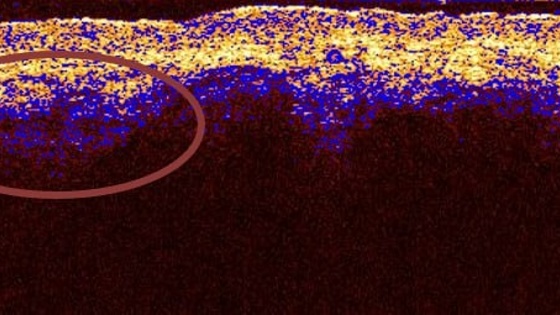

Софт выполнен на основе технологии оптической когерентной томографии. Он позволит медикам проводить бесконтактную оптическую биопсию ожогов в реальном времени с высокой точностью. Разработка поможет врачам более точно определять степень повреждения кожи и устанавливать тактику лечения.

Представленное специалистами ННГУ приложение Lumen stratis станет инструментом для визуального статистического анализа изображений структуры кожи. Ключевым преимуществом ПО является возможность использовать его напрямую «у постели» пациента».